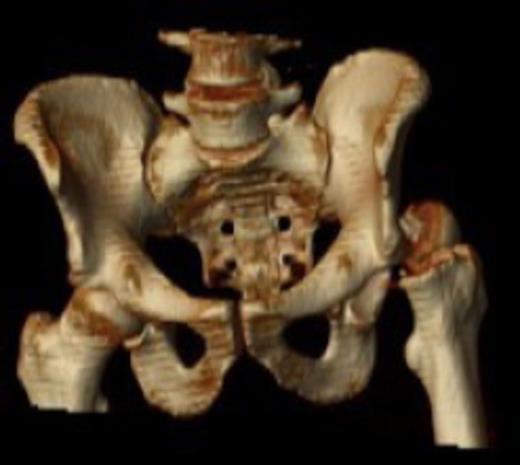

Posterior dislocation of the femoral head with no associated acetabular fracture

Antero-posterior radiograph of the pelvis confirmed a displaced transcervical femoral neck fracture with associated dislocation of the femoral head. Computed-tomography, confirmed a posterior dislocation of the femoral head with no associated acetabular fracture (Fig. 1,2,3).